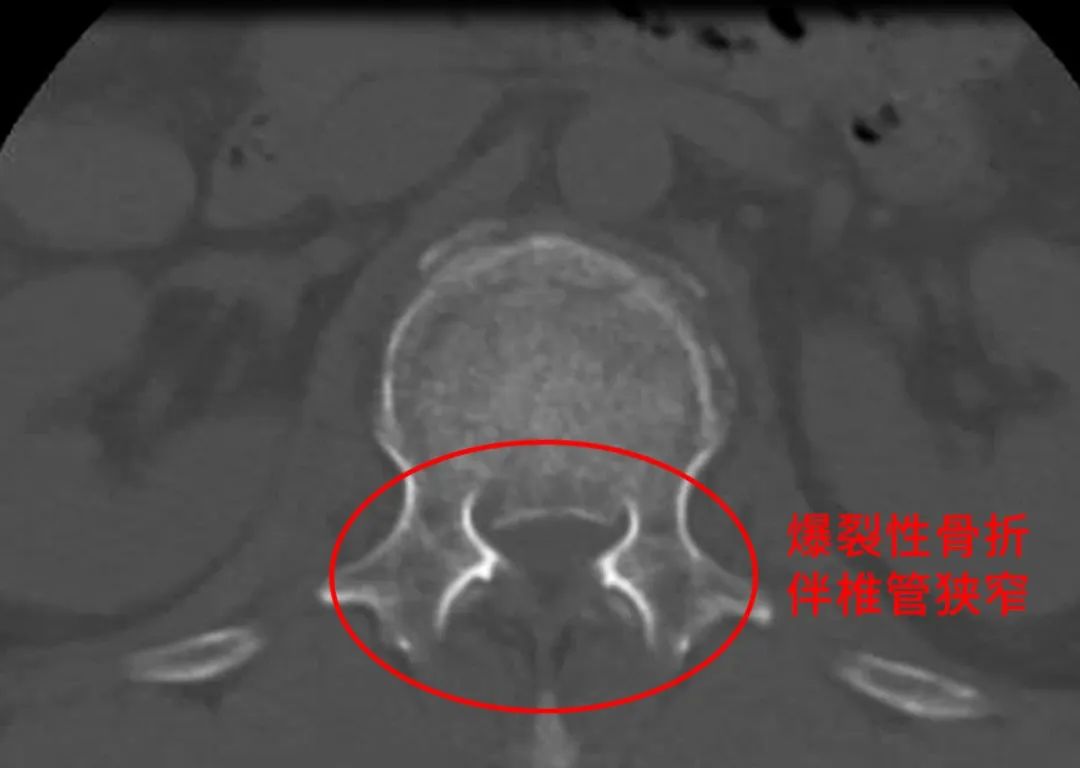

一场突如其来的车祸,让54岁的张女士陷入生死危机。腰背部剧烈疼痛、无法活动,急诊CT结果更是令人揪心 —— 腰1椎体爆裂性骨折,碎裂骨块突入椎管,造成椎管狭窄达50%!这种情况常伴随脊髓损伤风险,若不及时干预,截瘫的阴影将笼罩余生。垂直暴力如同恶魔之手,将张女士的椎体无情地 “粉碎性爆裂”,四散的骨块如锋利的刀片,直逼脆弱的神经。椎体高度丢失超过50%,脊柱的稳定大厦轰然崩塌;椎管容积的减少,让马尾神经时刻面临着被压迫的致命威胁。每一秒的拖延,都可能让张女士与正常生活渐行渐远。危急时刻,骨与创伤中心B区团队迅速集结,一场与时间赛跑的生命救援就此展开!「经后路腰1椎体切开复位内固定术」刻不容缓。手术中,专家们化身 “生命守护者”,步步为营: